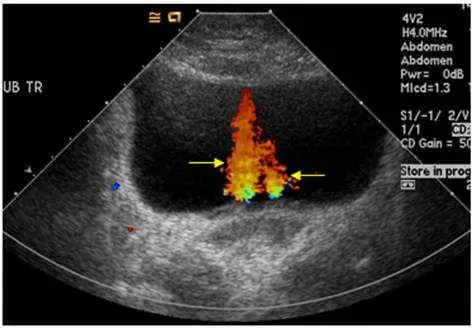

附圖為一張橫向(Transverse)的膀胱彩色都卜勒超音波影像。

- 背景結構:影像中央大片無回音(Anechoic,黑色)的區域為充滿尿液的膀胱(Urinary bladder)。

- 彩色都卜勒訊號:在膀胱後壁(接近膀胱三角區,Bladder trigone)的位置,可見一束呈現紅、黃、綠相間的彩色訊號向膀胱腔內噴射。

- 箭號指示:黃色箭號精準地指著這道彩色水流訊號。此訊號並非血管內的血流,而是尿液藉由輸尿管的蠕動,從輸尿管口(Ureteral orifice)間歇性地被擠壓、噴射進入膀胱腔內的過程,在臨床上稱為「輸尿管噴射現象」(Ureteral jet phenomenon)。